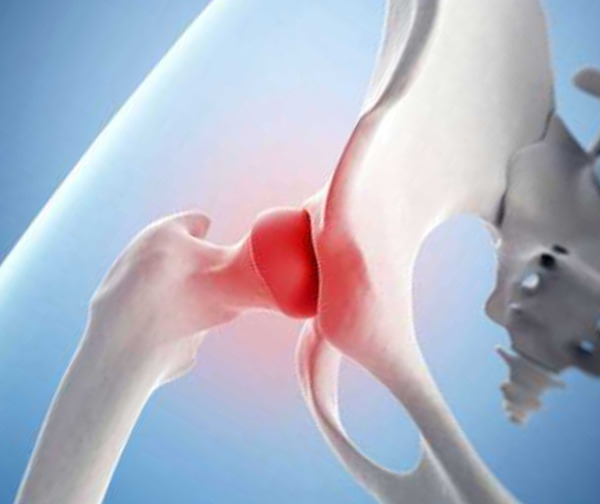

Здоровье суставов: Трохантерит и его влияние на мышцы